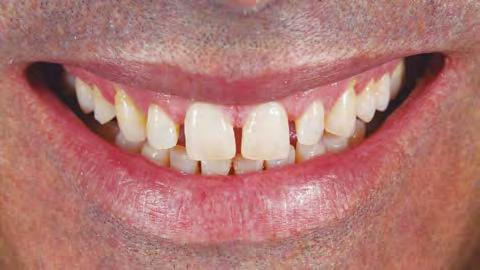

Como asegura el Dr. Solano, «el flujo digital facilita la comunicación con el paciente al poderle mostrar la planificación y los previsibles resultados que se obtendrán». Dr. Enrique Solano Reina